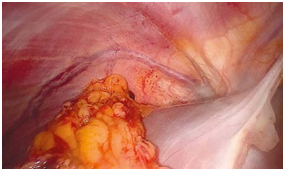

The first stage of omentoplasty was preparation of a flap of greater omentum (GO). Mobilization of the GO was performed through an upper median laparotomy. The entire GO was used. A pedicle was formed using the right gastroepiploic blood vessels. The GO was separated from the transverse colon in a vascular part of the gastrocolic ligament. The left gastroepiploic vessels were cut near the spleen. The GO was separated from the stomach by cutting the rectus rami and saving the gastroepiploic vessel arch in the omentum Figures D1 & D2. When preparing the right-side omental flap, it is important to mobilize the GO along a wide curve distal to the pylorus to prevent stomach deformation due to traction on the GO after transposition into the pleural cavity. The mobilized GO was transposed into the right pleural cavity through an incision in the right diaphragm .The site of this incision was chosen so as to ensure a straight position of the omental pedicle (without angulation)1 Figures D3 & D4. Thoracotomy was not needed in this case because the main problem was the residual space while the bronchial fistula was mild. The size of the incision must be suitable for the size of the omental flap ,to prevent neither omental strangulation nor diaphragmatic hernia, the omental flap was not fixed to the diaphragm by any suture because the negative pressure in the chest prevent the flap from withdrawing back to the abdomen. Follow up was wonderful:

D3 The incision in the right diaphragm

D4 The omental flap trasnsposisioned into the thoracic cavity